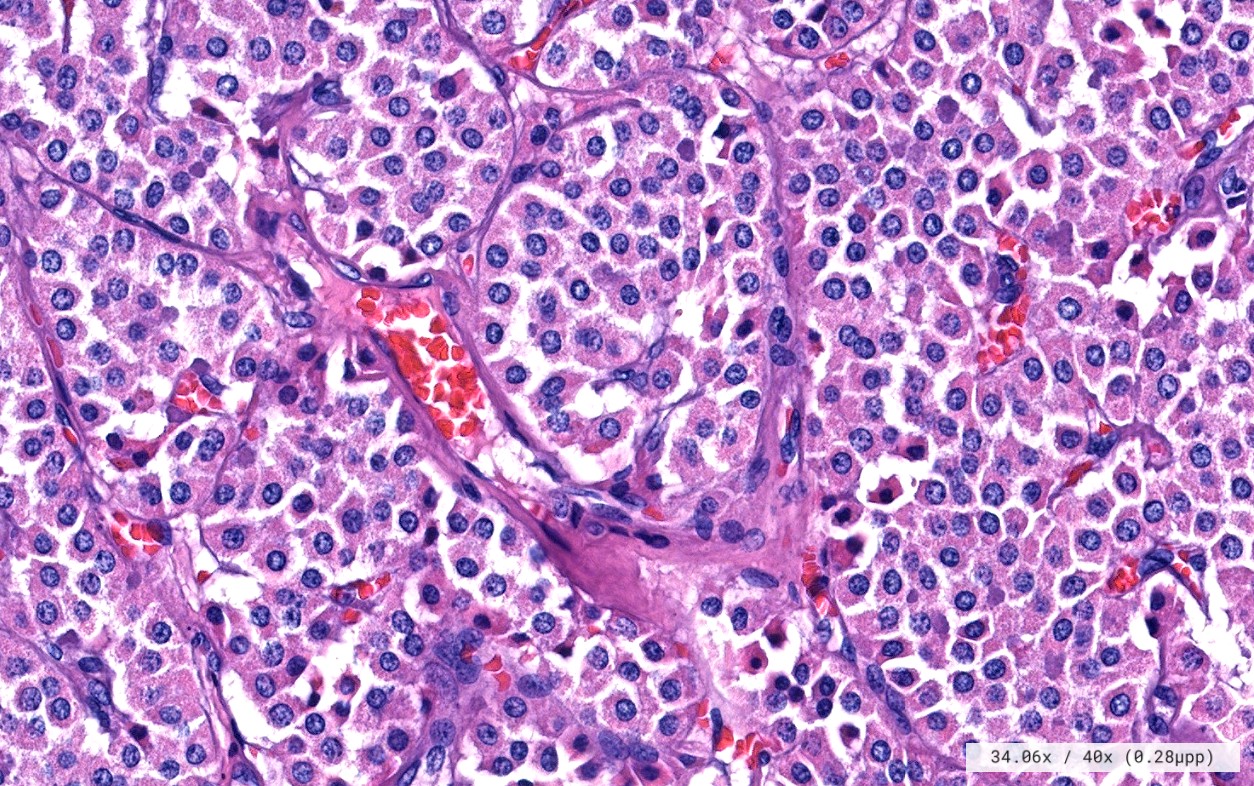

El diagnóstico sobre muestras de tejidos y líquidos corporales en plena era de la medicina del futuro, está basado en la integración de técnicas y conocimientos diferentes.

Hoy más que nunca es importante integrar una buena historia clínica con un correcto estudio de imagen y una buena morfología que además puede estar apoyada con proceso especiales complementarios relacionados con la Inmunología, Biología Molecular y Citogenética, generando así un estudio integral conocido como Patología Molecular.